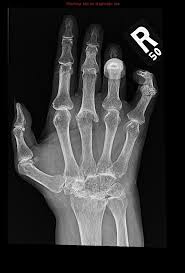

If the pattern of disease is not symmetrical, then a different diagnosis should be considered. Imaging tests you may get. The 2010 rheumatoid arthritis classification criteria help doctors diagnose rheumatoid arthritis. The ulnar styloid is destroyed with the rest of the distal ulna (white arrow), there is destruction of the carpal bones (yellow arrow) and there is dislocation of the 1st metacarpal on the destroyed trapezium. It can affect anyone of any age. Rheumatoid arthritis (ra) is a chronic autoimmune multisystemic inflammatory disease that affects many organs but predominantly attacks the synovial tissues and joints. Rheumatoid arthritis affects around 400,000 adults aged 16 and over in the uk. Rheumatoid arthritis can be difficult to diagnose because many conditions cause joint stiffness and inflammation and there's no definitive test for the condition. Ra causes pain, swelling, stiffness, and loss of function in joints. Rheumatoid arthritis is an inflammatory arthritis affecting both small and large joints in a symmetric distribution. Rheumatoid arthritis is an immune system condition, or autoimmune disorder, that causes inflammation of the lining of the joints. Rheumatoid arthritis is a chronic inflammatory disorder that can affect more than just your joints. Rheumatoid arthritis manifests as a symmetrical arthritis, most commonly affecting the hands.

If the pattern of disease is not symmetrical, then a different diagnosis should be considered. In rheumatoid arthritis, the body's immune system attacks its own healthy cells inside certain joints, leading to an inflammatory response. For more information and past images of the month, go to. However, they are not useful in the early stages of rheumatoid arthritis, before joint damage occurs. </b>rheumatoid arthritis (ra) is a polyarticular disease with bilateral and symmetric distribution. Sorptiometry should be performed to diagnose. The rheumatoid community on reddit. Rheumatoid arthritis (present for >10 years). The ulnar styloid is destroyed with the rest of the distal ulna (white arrow), there is destruction of the carpal bones (yellow arrow) and there is dislocation of the 1st metacarpal on the destroyed trapezium. Rheumatoid arthritis affects around 400,000 adults aged 16 and over in the uk. Reddit gives you the best of the internet in one place. Ra causes pain, swelling, stiffness, and loss of function in joints. The earliest manifestation of rheumatoid arthritis of the forefoot is synovitis of the mtp joints with eventual hyperextension deformity of the mtp joints including distal.

It can affect anyone of any age. </b>small joints of the feet, wrists, and hands are frequently involved by a reduction of osteoporosis; Severe rheumatoid arthritis of the wrist and hand. Rheumatoid arthritis (ra) imaging tests are used to look for signs of ra and to monitor the disease's progression. Ra causes pain, swelling, stiffness, and loss of function in joints.